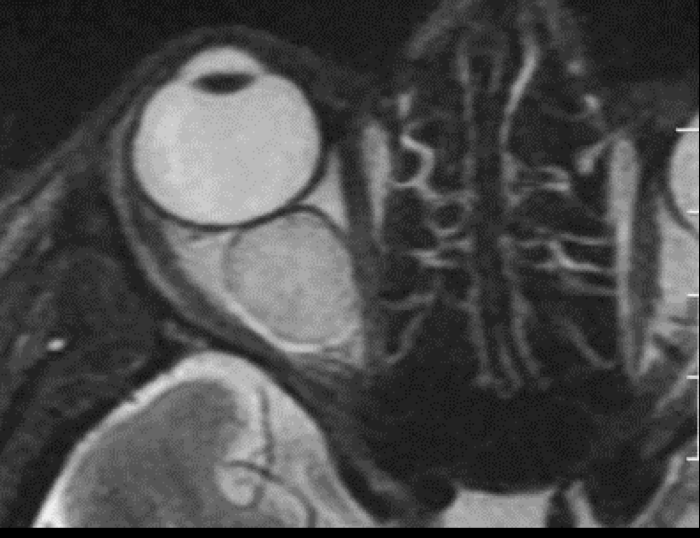

7

Q

T1: Agrandamiento de músculos

extraoculares.

T2: Aumento de señal en músculos extraoculares en fases agudas.

A

8

Orbitopatia tiroidea en RM